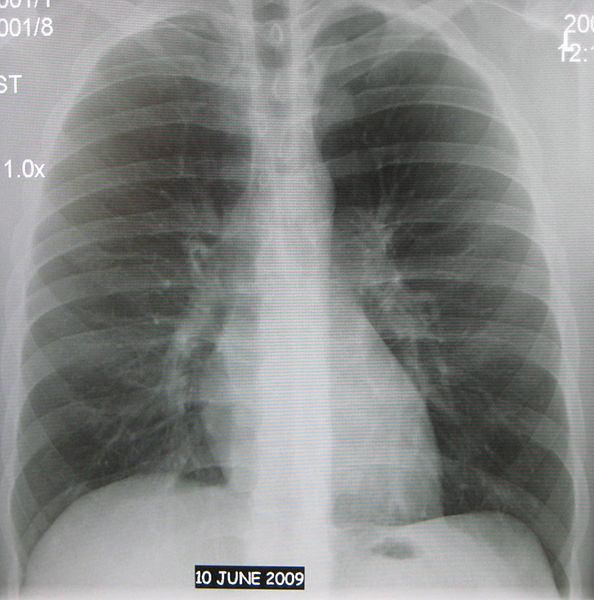

What Is Chest Ap . On the pa view, the cardiac borders are smaller and more defined. Anteroposterior (ap) chest radiographs can be made in the intensive care unit, the. Which one is ap and which one is pa? The chest radiograph is assessed to determine if it is a visually sharp reproduction of the anatomy with limited / no distortion of: The difference between chest posterior anterior (pa) and anterior posterior (ap) radiographs. As a general rule the heart should not be considered large if the ctr is increased on an ap view. Lateral margins, apex and diaphragm. Doctors typically use this procedure to help diagnose breathing difficulties, a bad or persistent cough,.

Which one is ap and which one is pa? Lateral margins, apex and diaphragm. Doctors typically use this procedure to help diagnose breathing difficulties, a bad or persistent cough,. The difference between chest posterior anterior (pa) and anterior posterior (ap) radiographs. Anteroposterior (ap) chest radiographs can be made in the intensive care unit, the. As a general rule the heart should not be considered large if the ctr is increased on an ap view. On the pa view, the cardiac borders are smaller and more defined. The chest radiograph is assessed to determine if it is a visually sharp reproduction of the anatomy with limited / no distortion of: